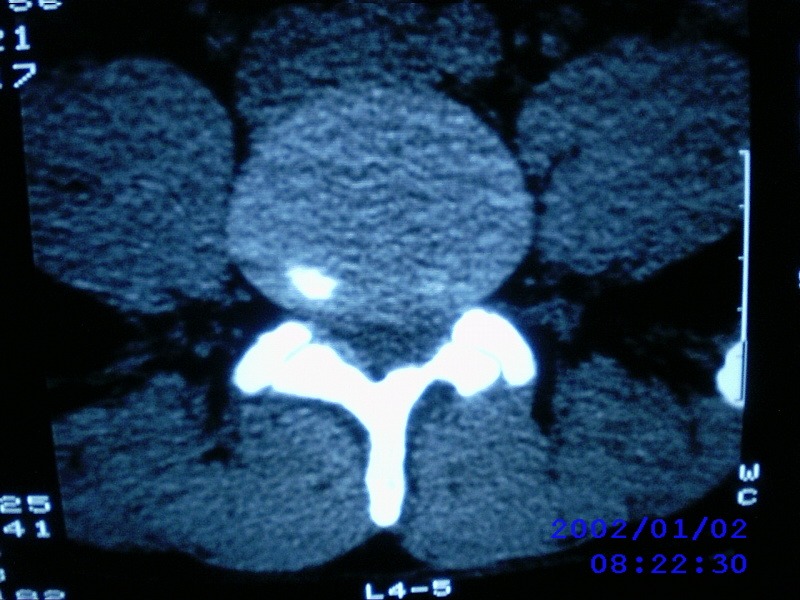

患者,男性,40岁,腰痛伴左下肢疼痛、麻木6年。5年前做过腰椎间盘手术,具体是哪个位置病人记不清了。

我拍的是l4-5、l5-s1

1)l4/5及l5/s1左侧椎板术后改变。2)l5/s1椎间盘突出,l5椎体下缘许莫氏结节。3)l4/5椎间盘膨出并突出。4)l3/4椎间盘膨出。

1)l4/5及l5/s1左侧椎板术后改变。2)l5/s1椎间盘突出,l5椎体下缘许莫氏结节。3)l4/5椎间盘膨出并突出。

1)l4/5及l5/s1左侧椎板术后改变。2)l5/s1椎间盘突出,l5椎体下缘许莫氏结节。3)l4/5椎间盘膨出并突出。4)l3/4椎间盘膨出。支持!